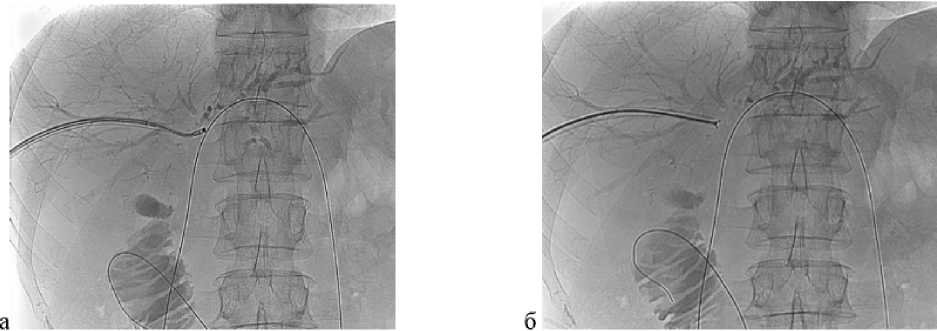

Рис. 1. Видеоассистированная внутрипротоковая щипковая биопсия под рентгеноскопическим контролем. а — рентгенограмма: ультратонкий эндоскоп установлен в месте выявленной опухоли на уровне конфлюенса общего печеночного протока; б — рентгенограмма: прицельная щипковая внутрипротоковая биопсия опухоли общего печеночного протока с использованием биопсийных щипцов

Рис. 2. Внутрипротоковая фотодинамическая терапия под рентгеноскопическим контролем. а — рентгенограмма: катетер с цилиндрическим диффузором заведен через правый долевой проток и расположен непосредственно на уровне опухоли, между дистальной и проксимальной рентгеноконтрастными метками (стрелки); б — рентгенограмма: катетер с цилиндрическим диффузором заведен через левый долевой проток и расположен непосредственно на уровне опухоли, между дистальной и проксимальной рентгеноконтрастными метками (стрелки)